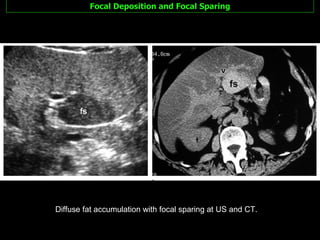

Focal Deposition and Focal Sparing Slightly less common More difficult to diagnosis because may  resemble mass lesions .

Focal Deposition and Focal Sparing Fat content Location  in areas characteristic of fat deposition or sparing Absence of a mass effect  on vessels and other liver structures A  geographic configuration  rather than a round or oval shape Poorly delineated margins Contrast enhancement that is  similar to or less than  that of the normal liver Imaging findings suggestive of  fatty pseudolesions  rather than true masses include the following:

Focal Deposition and Focal Sparing Adjacent to the  falciform ligament   In the  porta hepatis In the  gallbladder fossa focal fat deposition or focal fat sparing characteristically occurs in specific areas: Focal fat deposition adjacent to  insulinoma metastases , probably due to local insulin  effects on hepatocyte triglyceride synthesis and accumulation.

Focal Deposition and Focal Sparing Diffuse fat accumulation with focal sparing at US and CT.

Focal Deposition andFocal Sparing Diffuse fat accumulation with focal sparing at US and CT.